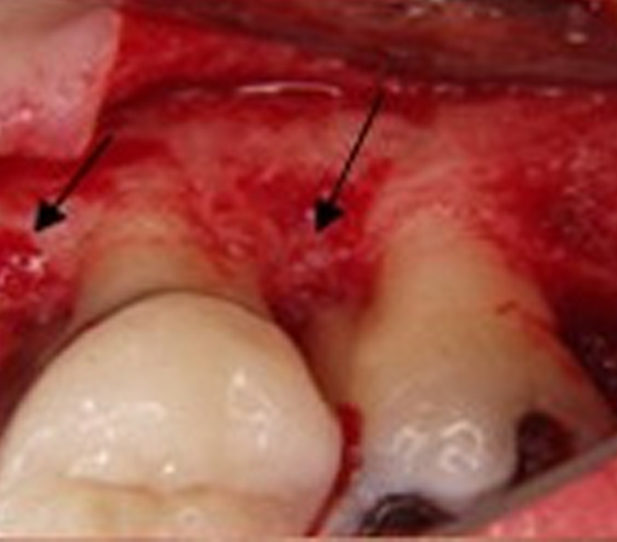

The gum is pulled up during this treatment, and the plaque is removed. In some cases, the irregular surfaces of the damaged bone are smoothed.

This limits the areas where pathogenic bacteria can hide. Then, the gums are placed so the gum tissue is wholly connected to the tooth. Removing the space between the gums and teeth also reduces the growth areas of harmful bacteria. The likelihood of severe health problems leading to periodontal disease is reduced.